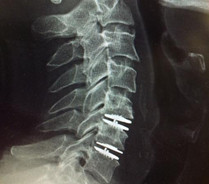

In discussions around Disc Replacement surgery in Mumbai, the team highlighted that not every patient with disc-related pain is a candidate. Careful evaluation—including imaging, neurological assessment, and response to conservative treatment—forms the backbone of decision-making. This cautious, layered approach reflects clinical maturity rather than procedural enthusiasm.

Disc Replacement Surgery in Mumbai: Clinical Benefits and Risks

Disc replacement surgery is designed to preserve motion at the affected spinal segment, unlike fusion procedures that limit movement. The potential benefits discussed during my interview included:

- Preservation of spinal mobility

- Reduced stress on adjacent spinal segments

- Faster return to functional activity for select patients

- Relief from chronic disc-related pain when conservative care fails